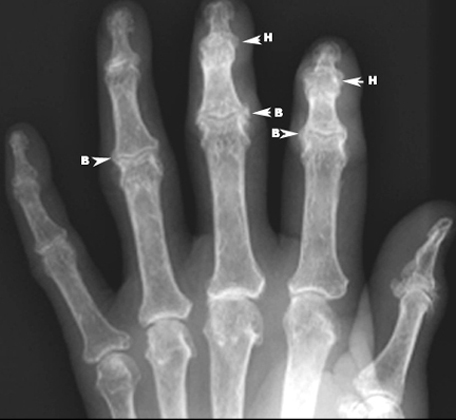

Osteoarthritis hand

• Cartilage loss with narrowing of interphalangeal joints

• B: Bouchard nodes (osteophytes proximal interphalangeal joints)

• H: Heberden nodes (osteophytes distal interphalangeal joints)